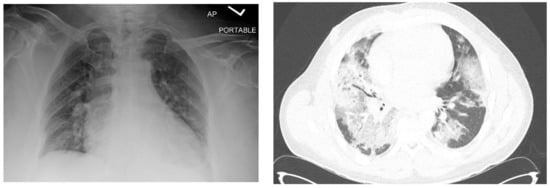

One month after finishing the last cycle of chemotherapy, the patient developed shortness of breath and a dry cough and was diagnosed with pneumonia, requiring readmission to the hospital. His initial oxygen saturation on room air was as low as 90%. He was given supplemental oxygen, ceftriaxone, and azithromycin. A CT scan revealed ground glass opacities and air bronchograms and re-demonstrated his retroperitoneal mass and liver lesion, both significantly smaller (Figure 1 and Figure 2).

Figure 2.

Chest radiograph (left) and axial image from chest CT (right) showing patchy opacifications on the day of admission.